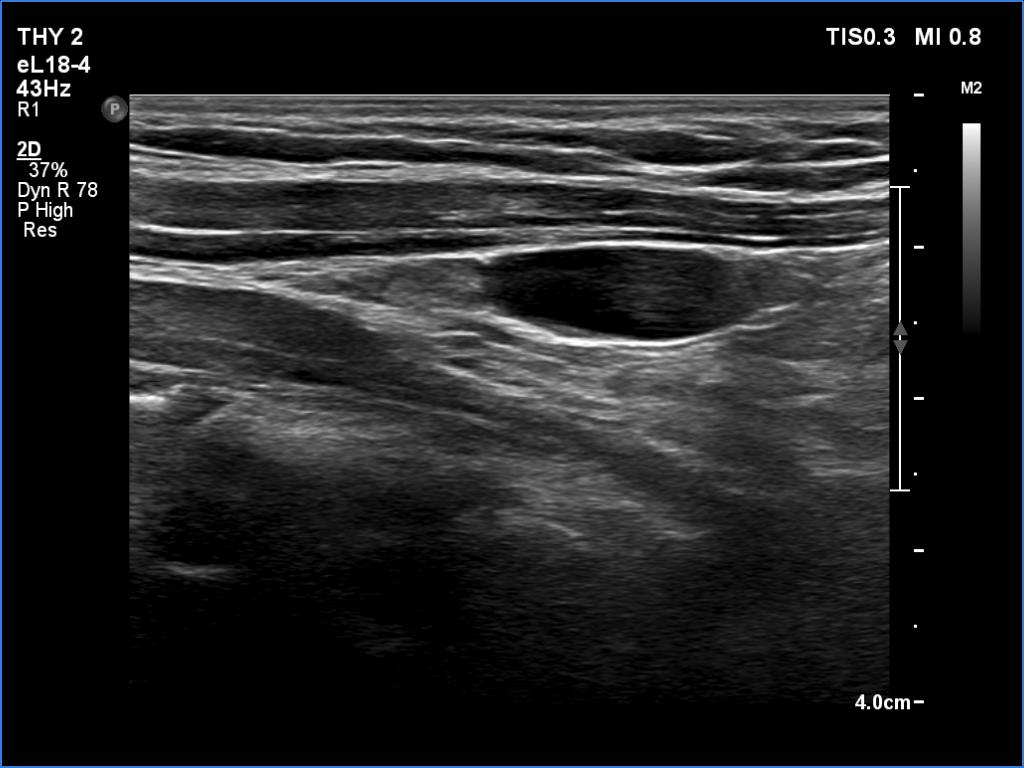

Follow-up investigation two years later (ultrasonographic picture 4)

Left lobe, longitudinal scan. Connective tissue can be seen in the upper fourth while a cystic lesion in the lower three-fourth of the thyroid bed.